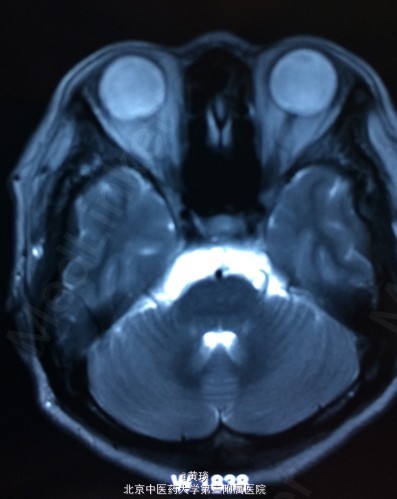

患者女,75岁,自诉压槽疼痛10年,未予重视,曾行封闭治疗无效,来我院,本来诊断为普通三叉神经痛,结果行MRI示:桥小脑角区占位,胆脂瘤,T1相高信号,T2相低信号,抑脂相高信号,压迫右侧三叉神经。

见图

诊断:胆脂瘤,继发三叉神经痛 处理:开颅切除胆脂瘤